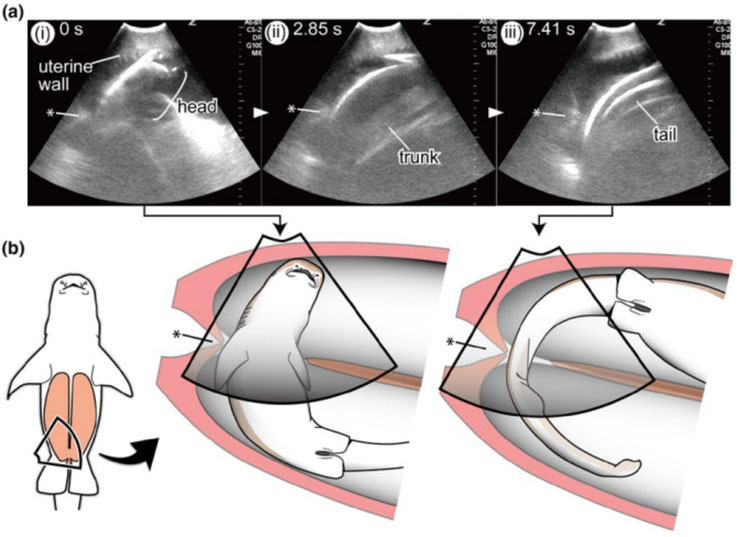

Gli ultrasuoni hanno rivelato qualcosa di incredibile: embrioni di squalo che si spostavano da uno dei due uteri all'altro (si, gli squali hanno due uteri). Più spesso, tuttavia, gli embrioni in movimento sono stati catturati dopo il fatto, quando cioè controllando uno squalo si scopriva che il numero totale di embrioni di squalo in un utero era diminuito, mentre il conteggio in un altro utero era aumentato della stessa quantità.

"I dati hanno anche dimostrato che la cervice dello squalo nutrice a volte si apre", hanno scritto i ricercatori, "e l'embrione tira fuori la testa dall'utero attraverso la cervice."

In altre parole, a volte gli embrioni di squalo nutrice fulvo non ancora nati decidono di dare un'occhiata al mondo esterno.

"Questo fenomeno è in contrasto con quello osservato nei mammiferi dove la cervice è strettamente chiusa fino alla nascita".